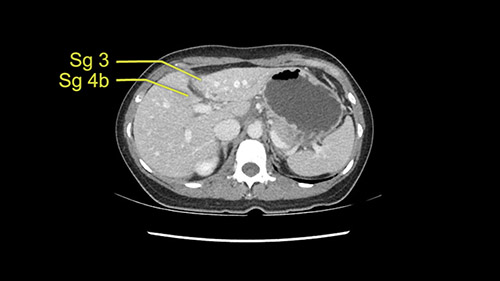

As I review the CT scan, we have both arterial and venous phases, the tumor is obvious. But I’ll start by saying that the liver itself does not appear to be cirrhotic to my eye. It’s got a normal contour and allied to that, that I do not see evidence of portal hypertension. The spleen is normal, there’s no collateral vessels. The tumor itself, I measured maximally at about 11 centimetres in diameter and I’m told the alpha fetoprotein is very high (over 10000), which is entirely consistent with this being a solitary hepatocellular carcinoma that is very exophytic. It seems to emanate off the inferior margin of Segment 3 (because that’s the falciform). I’ll start by saying that this is not transplantable. The tumor exceeds our guidelines for transplantation, but it's likely resectable based on normal liver and no portal hypertension.

So the issue with regards to resection. A left sided tumor. I believe I can see the falciform ligament right here so we’re looking at a resection of Segments 2, 3 of the left lobe of the liver. The left portal vein is right there. I think we’ll be wiser to take the left portal vein and therefore get well into Segment 4 and do a left hemihepatectomy. Certainly, one does not need to take the middle hepatic vein; it’s miles from the tumor.

We note that the tumor is pushing on the gallbladder but I think that’s probably external for the most part. I think that’s extrahepatic. I believe that Segment 4b is probably free of tumor. I’d have to say that it's tempting, particularly looking at the coronals, to consider a very limited resection. Where you’d just chip it off the bottom of Segment 3 and do a limited Segment 3 resection. I’d be concerned about the oncologic margins. I believe that the best oncologic operation will be to take the left portal vein to get this. Certainly, she’s got plenty of liver and she’d be able to sacrifice Segments 2-3 of the left lobe of the liver. It’s not necessary to take too much of thus of Segment 4a. But once one takes the portal vein, that will be compromised. So I would do a left hemihepatectomy on this woman.

The tumor is so close to the falciform ligament, I had a question mark about the Segment 4b relation between segment 4b and segment 3. In a normal resection of segment 2 and 3, we would be keeping on the left side of the falciform ligament and start getting segment 3 and 2 portal pedicles but in here its getting so close. So oncologically, 4b should be checked during the OR.